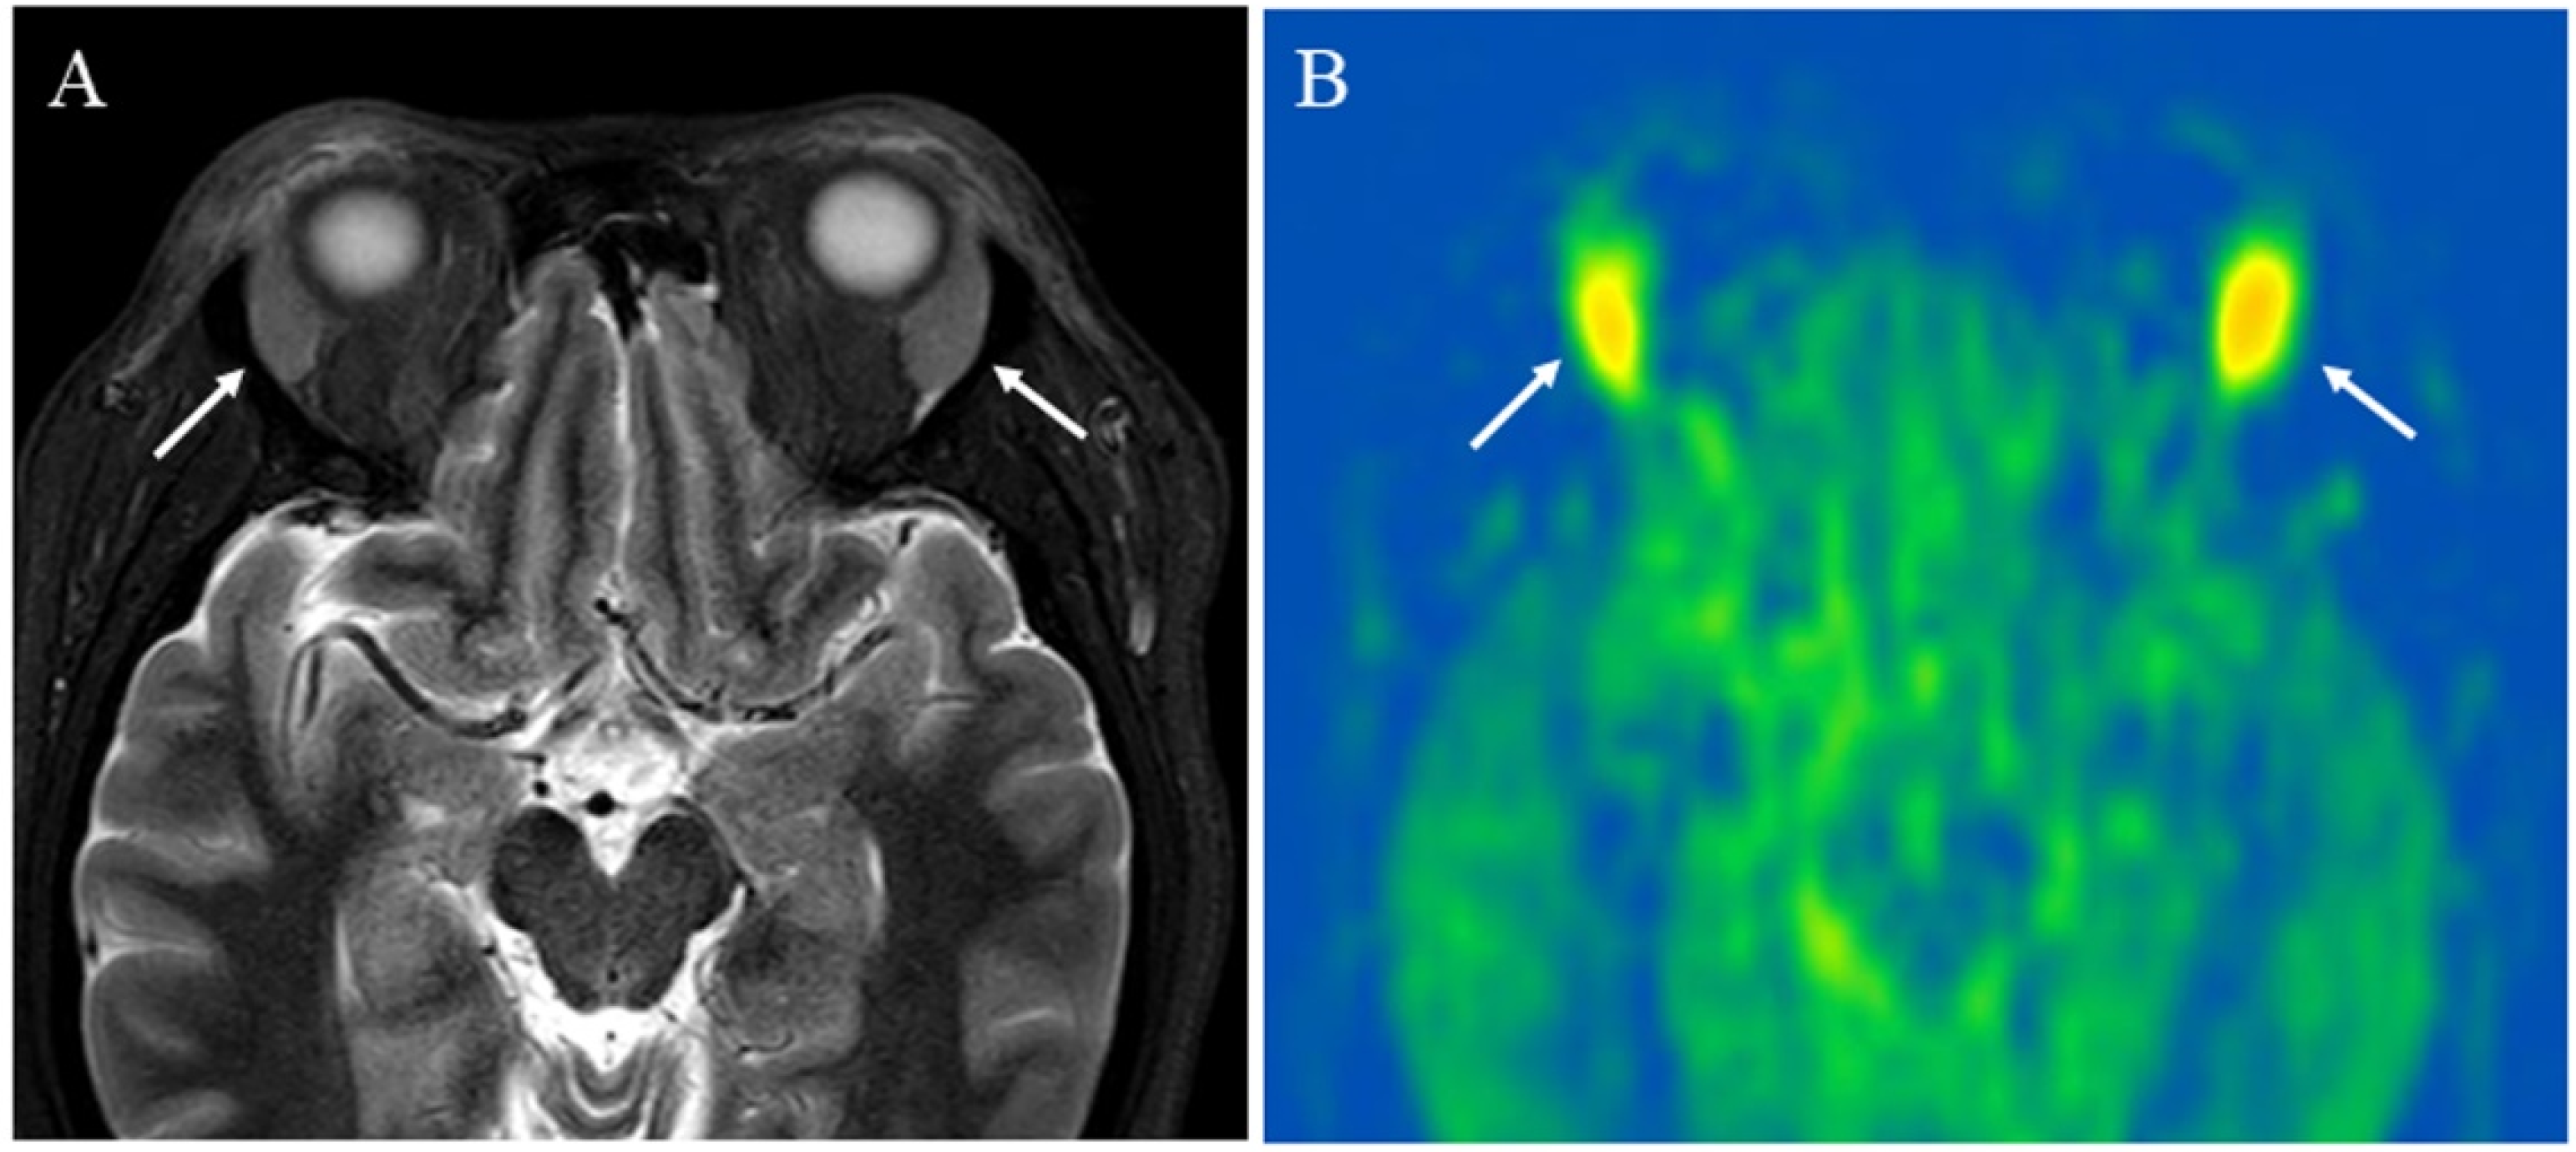

Figure 5. A 43-year-old female with immunoglobulin G4-related disease that involves the bilateral lacrimal gland: (A) Short tau inversion recovery (STIR) shows bilaterally enlarged lacrimal glands with high signal intensity (arrows); (B) pCASL image shows high blood flow within the lesions (arrows) (right mean of 65.70 mL/100 g/min and left mean of 66.98 mL/100 g/min).